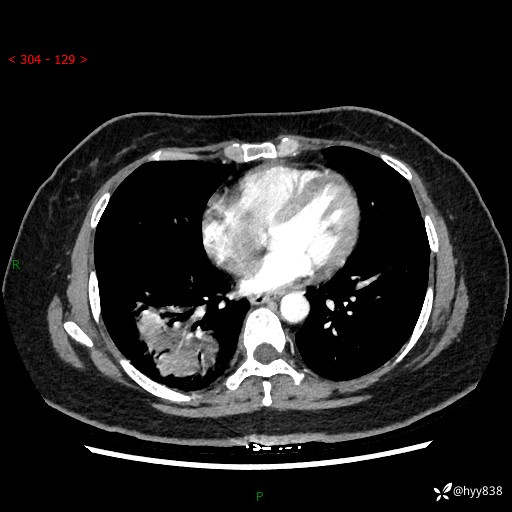

增强动脉期+静脉期